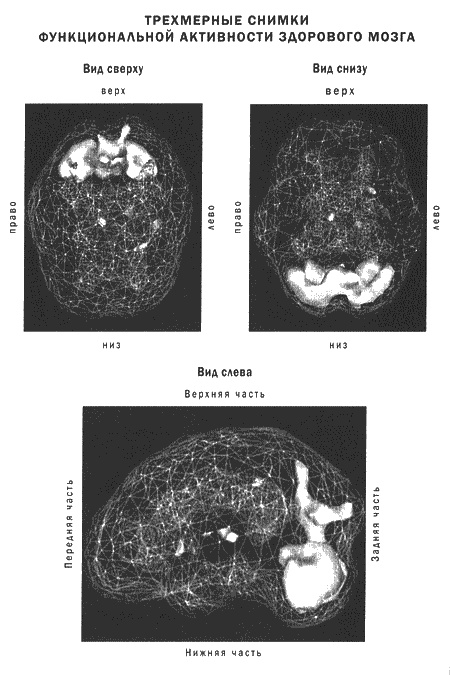

Томограммы четко показывают, что депрессия сопровождается дисфункциями в эмоциональных и когнитивных центрах мозга.

Исследователи сканировали мозг буддистских монахов во время длительной медитации. Чтобы увидеть активность мозга, ученые ввели каждому испытуемому слабый раствор радиоактивных веществ, которые быстро поглощаются нейронами, а их невральная активность отслеживается при этом камерами ОЭКТ. Снимки показали, что при переходе в медитацию в работе мозга происходят отчетливые изменения. В частности, падает активность в областях мозга, которые отвечают за трехмерную ориентацию в пространстве. Это может объяснить ощущение «освобождения» и «парения» во время медитации. Некоторые исследователи предполагают, что элементы религиозных переживаний трансцендентного тоже могут быть заложены в мозге на уровне структур.

В трех следующих главах я расскажу о пяти системах мозга, которые связаны со взаимоотношениями, работой и духовным ростом. Это: кора лобных долей, передняя часть поясной извилины, базальные ганглии, височные доли и лимбическая система. Я расскажу о функционировании и возможных проблемах в работе каждой из этих областей, а также об их роли в восприятии добра, зла, любви и в здоровье души. Разумеется, вся теория будет проиллюстрирована историями и сканограммами ОЭКТ.